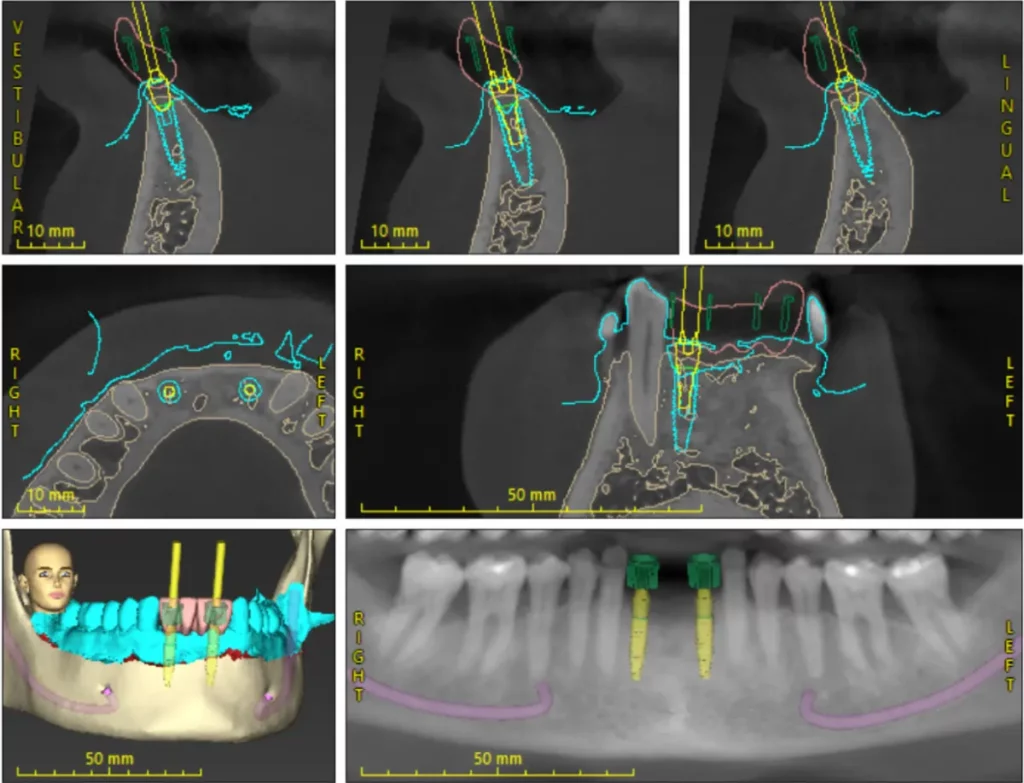

Mediante un TAC dental en 3D y un escáner intraoral, analizamos la anatomía del paciente y planificamos la posición exacta de los implantes en función de la planificación protésica.

A partir de esta planificación se fabrica una férula quirúrgica personalizada que guía la colocación de los implantes durante la intervención con una precisión milimétrica.

Mediante software especializado planificamos la posición ideal de los implantes teniendo en cuenta la futura prótesis dental.

Esto permite diseñar el tratamiento con máxima precisión antes de la cirugía.